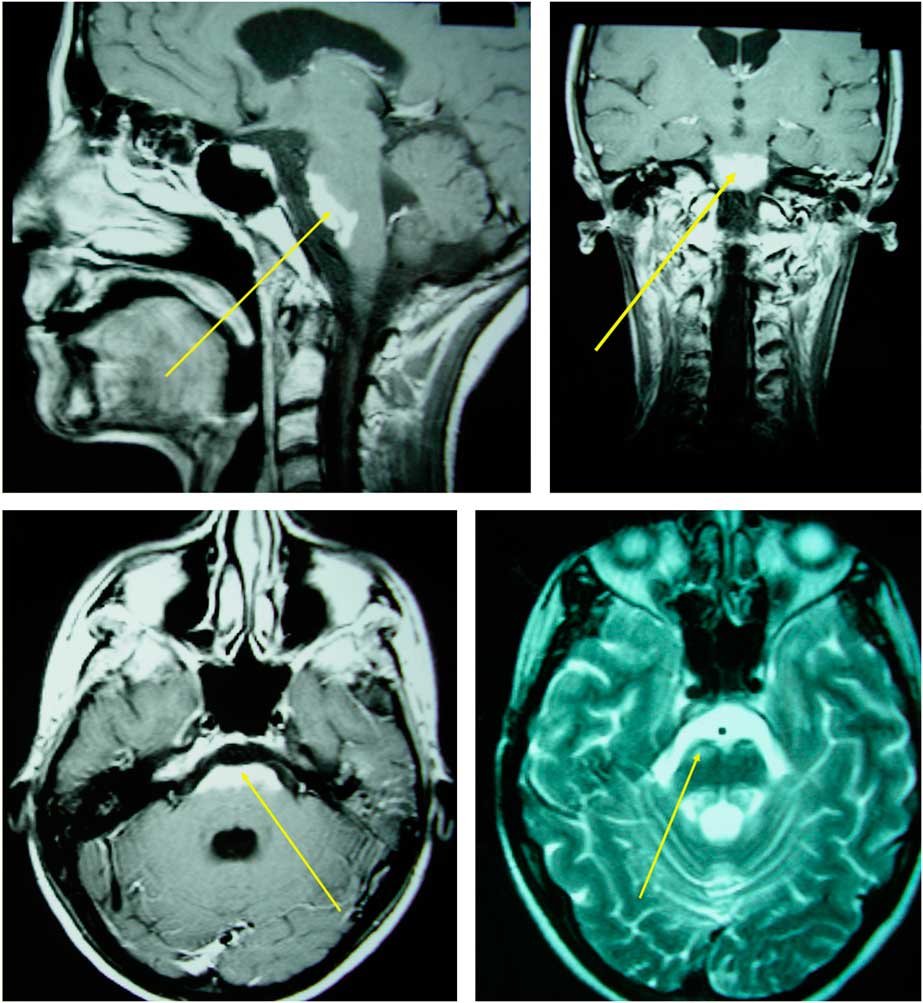

A 28-year-old female was admitted with a progressive gait disturbance, difficulty in swallowing, diplopia, and dysphonia. The neurological examination showed severe spastic paraparesis, pyramidal signs on the upper limbs, hoarseness, paresis of the left VI and VII, and bilateral impairment of all the lower cranial nerves. During examination of her medical history, she reported diabetes as well as nasopharyngeal carcinoma, for which she had undergone radiotherapy 1.5 years ago. She received a total dose of 63 Gy in 2-Gy fractions in three phases, which lasted for a period of 7 weeks. MRI revealed an extended lesion to the brainstem from midbrain to the medulla oblongata, which was shown to be hypointense on T1 and hyperintense on T2. This lesion presented a marked homogenous enhancement (Figure 1). The results of her standard biochemical examination were found normal. She was treated with 1 gr of methylprednizolone for 5 days, followed by gradual reduction of the dose. After 2 months of corticosteroid treatment, a mild clinical improvement was observed

Figure 1 Extended brainstem lesion characterized by T2 hyperintensity and homogenous enhancement in T1 C+ (Gd) imaging.